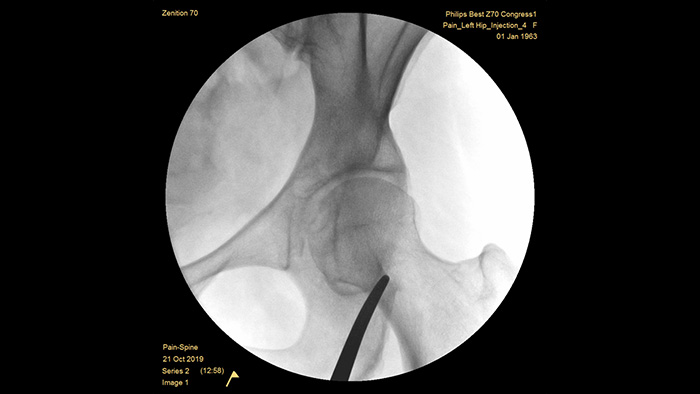

Zenition 70 Mobile C-arm with Flat Detector

Enhance image quality and dose efficiency in complex and dense anatomy

With our fourth generation Flat Detector systems, you gain exceptional image clarity of dense and complex anatomy. The compact form provides ample space and positioning ease for treating chronic pain in the joints. Our Position Memory2 increases first-time-right positioning to reduce scout images3 for efficient workflow in pain management cases.

The Zenition 70 is available in two detector sizes: the FD 26 cm x 26 cm offers broad anatomical coverage, while the FD 21 cm x 21 cm provides ample space to work around patients.